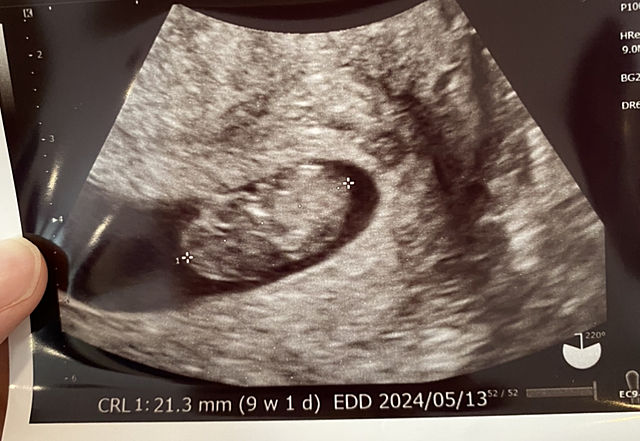

産婦人科![]()

ただいま、9週と1日らしいです![]()

予定日もわかり、5月13日だそうです![]()

しっかり、心拍も確認できました![]()